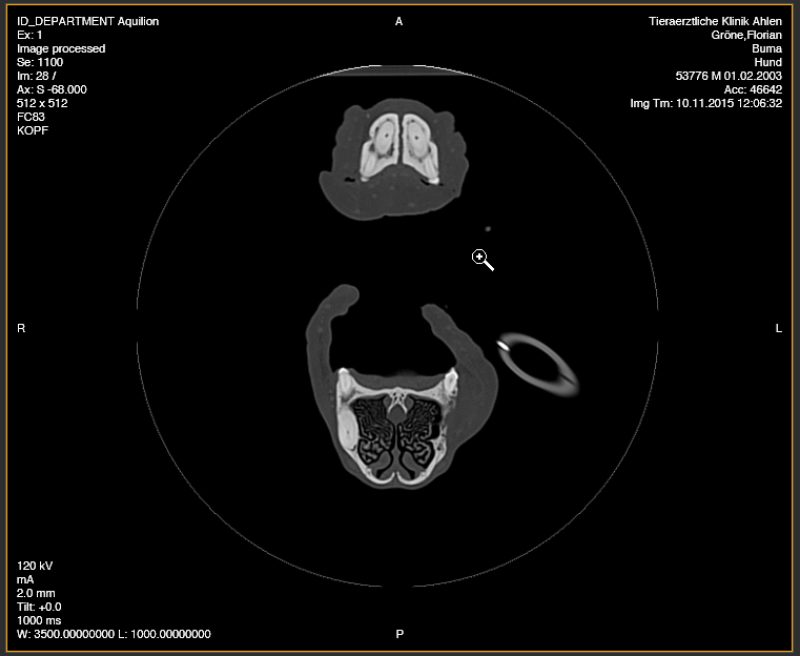

Um die Operation sinnvoll planen zu können war es wichtig zu wissen, wie der darunterliegende Knochen aussah - ob der Tumor bereits begonnen hatte, diesen zu zerstören und wie weit der Tumor sich auch im umliegenden Weichteilgewebe ausgebreitet hatte. Daher wurde bei Buma zunächst eine Computertomographie (CT) durchgeführt. Der CT-Befund zeigte eine Knochenbeteiligung im Bereich des zweiten Backenzahnes, jedoch weder einen Einbruch in die Nasenhöhle noch eine Veränderung der zuständigen Lymphknoten.

Anhand der 3D-Rekonstruktionen der Computertomographie wurde ein Operationsplan erstellt. Aufgrund der Tumorart war klar, dass es nicht ausreichen würde den Tumor nur oberflächlich bzw. mit geringem Abstand zu entfernen. Daher wurde die Entfernung des linken Oberkieferknochens inklusive der Zahnreihe beginnend vom dritten Schneidezahn bis zum großen Reisszahn (P4) geplant.